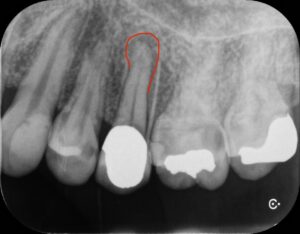

左上の前歯の痛みを主訴に当院を受診されました。レントゲン写真にて赤い線の部分が膿んでいるのが確認できましたので、神経の治療(根管治療)を行いました。

最終的なお薬を入れた直後のレントゲン写真です。まだ赤い線の部分の状態は変わっていません。

こちらが2年経過後のレントゲン写真になります。赤い線の部分は完全に膿が消え、骨が再生しています。患者さんも症状が全くなく快適に過ごしているようで良かったです。

これからも定期的に経過を追っていきたいと思います。